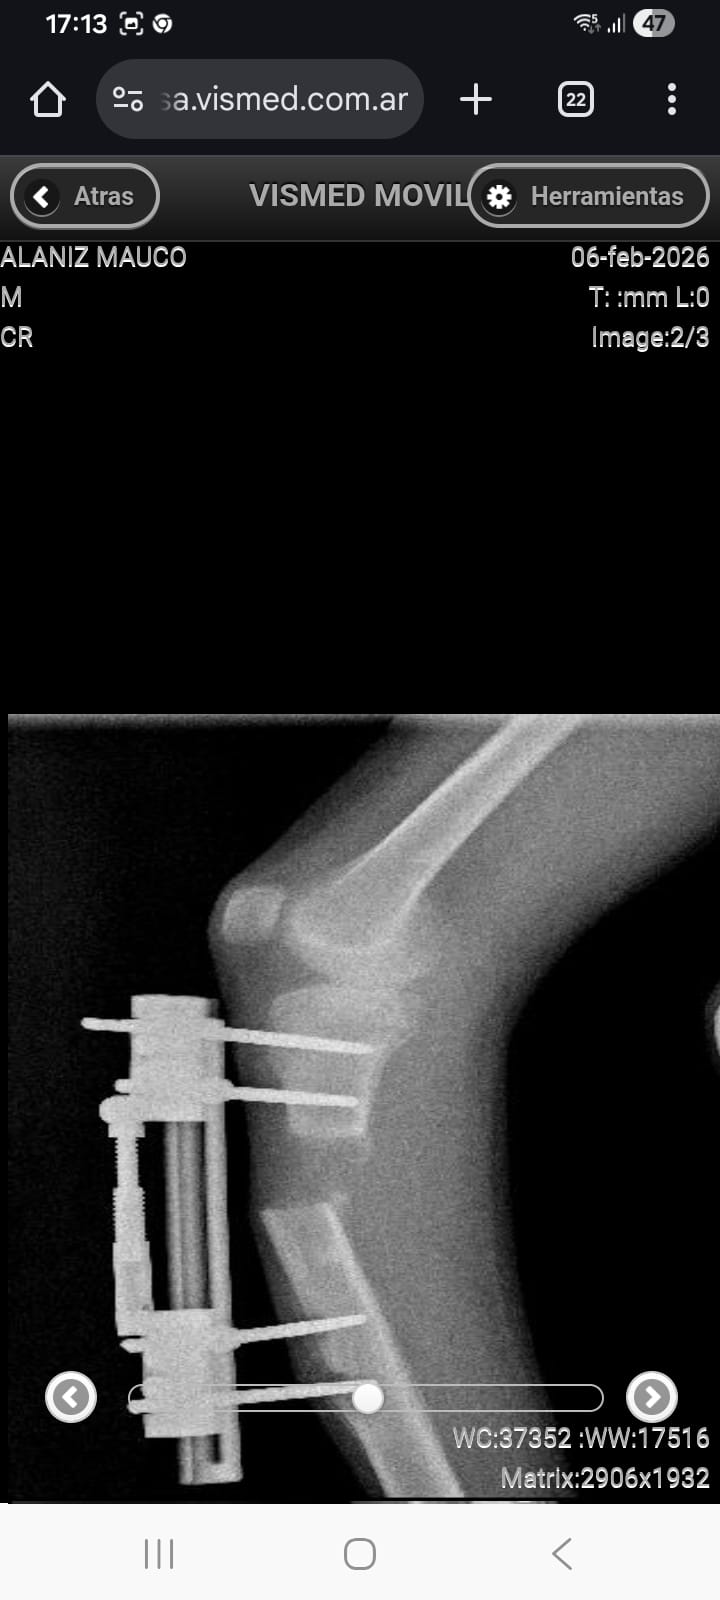

El padre del joven explicó cuál es el problema que afronta su hijo: «Mi hijo nació con una malformación congénita, en donde no tiene el peroné y hace que tenga una diferencia de 7 centímetros con su otra pierna. Ya vamos a llevar 13 operaciones con la de este viernes, y hace un mes y medio lo operamos para hacerle un alargamiento de tibia, pero lamentablemente su hueso se corrió de lugar y es por eso que tiene que ser operado de urgencia para ser corregido y seguir con su tratamiento que lleva más de un año».

Por otro lado, Alfredo manifestó que todas las operaciones de su hijo son ambulatorias, por lo que se encuentra con internación domiciliaria y la intervención quirúrgica se realizará en el Centro Médico Tótem de San Martín. Además, añadió: «Tenemos que pagar quirófano porque su médico no tiene uno propio y también sus ayudantes».